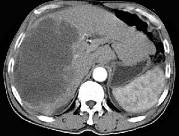

问题 男,62岁,右上腹痛半年,腹部包块,黄疸较重,AFP阴性,CT检查如图,最可能的诊断为()

选项 A.原发性肝癌 B.胆管上皮癌 C.肝囊肿 D.肝脓肿 E.肝错构瘤

答案 B